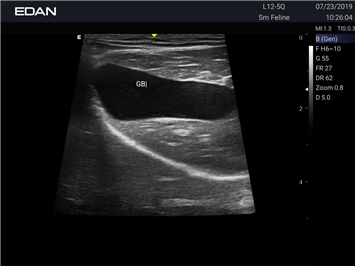

Ветеринарный ультразвук одним нажатием. Система Acclarix AX3 VET разработана с целью обеспечить бескомпромиссную производительность по доступной цене. Наличие уникальных двойных разъемов и двойных аккумуляторов в легком корпусе массой 4,5 кг из магниевого сплава позволяет системе Acclarix AX3 VET удовлетворять все потребности ветеринарных исследований, сохранив низкую стоимость.

EDAN Acclarix AX3 VET - это компактная ультразвуковая система, специально разработанная для ветеринарной практики, сочетающая высокую производительность с доступной ценой.

• Специальные настройки для исследования животных разных видов

• Специализированные предустановки для ветеринарных исследований